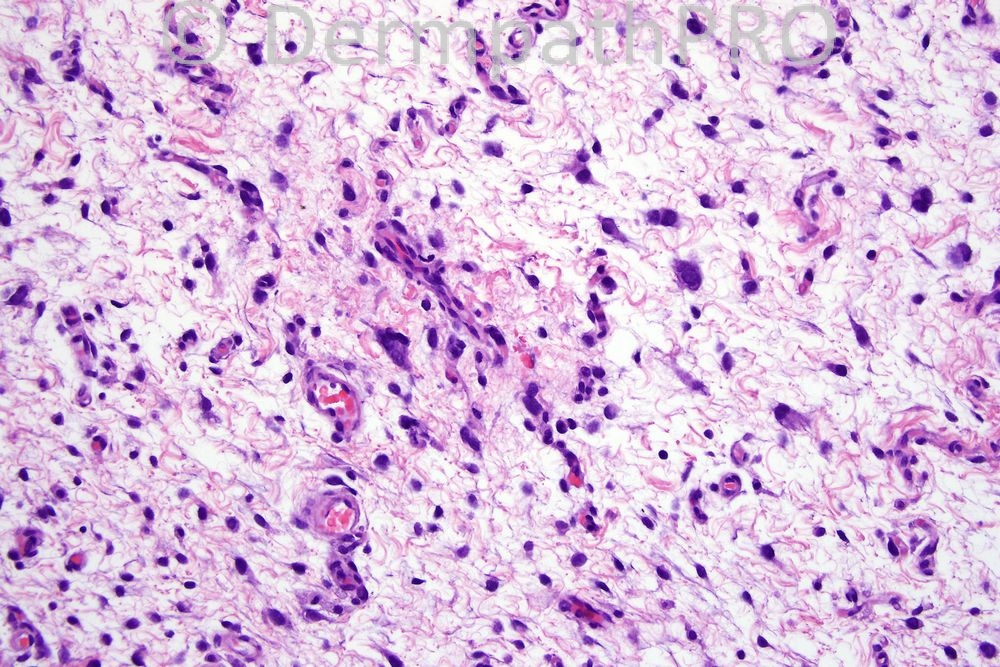

Recurrent tumor on leg.

Pleomorphic spindle and polygonal cells in a myxoid stroma and conspicuous 'curvilinear' vessels. I think this is a MYXOFIBROSARCOMA (myxoid MFH). I don't think this is a myxoid liposarcoma or an angiomyxoma as the cells are too pleomorphic and a dermal/subcuticular location would be unusual for a myxoid LPS. I would expect S100 to be negative and CD34 /actins and CD68 to show variable positivity.

I think that there are curvilinear vessels best seen at low power. This is a case that preceeded the immunohistochemistry era. I think however that it fits best with myxoid MFH but obviously could be wrong!!!!

Myxoid tumour with pleomorphic cells and abundant vasculature. Don't see curvilinear vessels but Myxofibrosarcoma (? high grade with the pleomorphic cells).